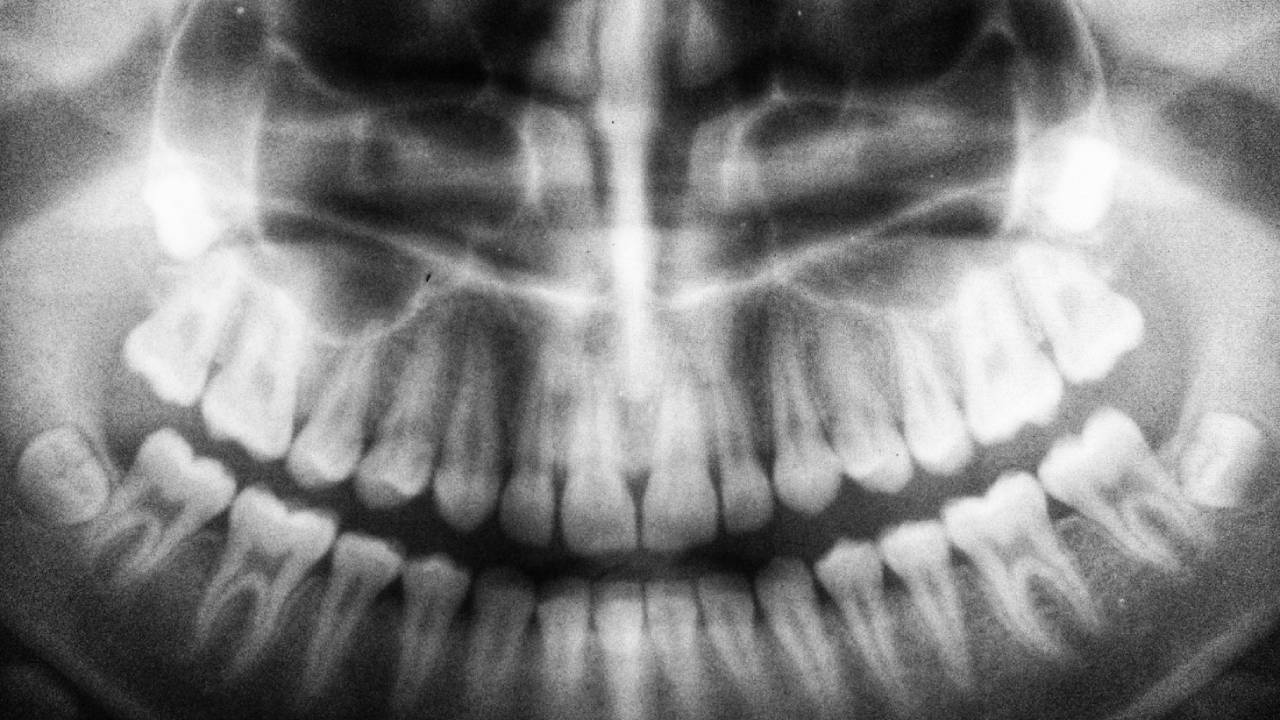

Uno de los cambios más notorios en la evolución dental humana es la disminución en la presencia de las muelas del juicio o terceros molares. El profesor Paul O’Higgins, supervisor del proyecto BioMan, explica que la incidencia de la agenesia del tercer molar (es decir, la ausencia congénita de estas piezas dentales) ha aumentado significativamente en los últimos siglos.

Los estudios muestran que la ausencia de estos dientes varía entre poblaciones. En África, la frecuencia de agenesia M3 es relativamente baja, mientras que en algunas regiones de Asia, incluyendo Japón, India, Turquía, Israel e Irak, la incidencia es más alta. La relación entre el tamaño de los molares y la agenesia M3 sugiere que la reducción en el tamaño de los dientes podría ser un factor clave en esta transformación evolutiva.

Curiosamente, las mujeres tienen un 14 % más de probabilidades de carecer de muelas del juicio que los hombres, según un estudio de Carter y Worthington. Este fenómeno podría estar relacionado con diferencias en el tamaño de los dientes entre sexos, aunque su explicación exacta sigue siendo un tema de debate en la antropología biológica.